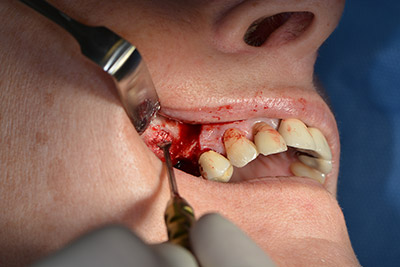

Im nächsten Schritt wird die Sinusbodenelevation mit simultaner Implantation durchgeführt. Für die bukkale Fensterung der Kieferhöhlenwand gibt es auch hier bei der Implantmed an der ersten Position eine Voreinstellung.

Mit 35.000/min wird das Fenster angelegt und anschließend die Schneidersche Membran nach kranial präpariert. (Abb. 13 bis 14).

Danach wird das Implantat eingebracht und der Knochen aufgebaut. Aufgrund der Größe des Augmentates wurde im vorliegenden Fall Eigenknochen, der als Bohrspäne bei der Implantation 16 und der Fenestration 14 angefallen ist und mit einer Knochenfalle aufgefangen wurde, mit Knochenersatzmaterial vermischt.